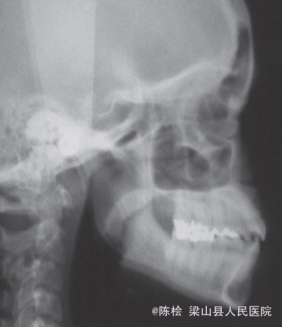

18岁女性,主诉前牙咬不到

伸舌吞咽习惯,前牙4-4开合3mm,上下牙列散隙

诊断:开合 治疗:双侧第一第二磨牙带环上制作TPA,同时弓丝伸至前牙段弯成腭刺,腭刺破除伸舌吞咽的不良习惯,TPA压低双侧后牙,降低后牙槽高度,改善开合.

对于开合病人,光是压低后牙可能效果不是很好,应把改不良习惯的装置一同考虑进去才能达到事半功倍的效果。该装置既包含腭刺又焊有TPA,一举两得,值得推广。